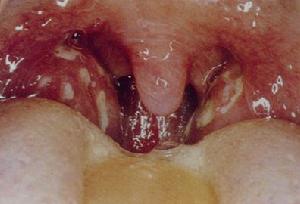

扁桃体肥大预防护理

扁桃体肥大预防护理?乌兰察布健民男科医院的谢雅斌主任介绍:扁桃体肥大实证:以消痰软坚为主。常用代表方有三子金灯汤。常用药:苏子、莱菔子、白芥子、挂金灯、桔梗、山慈姑、六曲、甘草。

此外,药食同源,尤其是儿童进药困难,运用食疗也是一个较好的办法,其中以芋艿为最理想。每天约吃200克左右,调味不论淡的、甜的、咸的、干蒸、炖煮、烧汤都可。连服3-6个月。次之为慈姑,因生长时间不长,四季难以为继,而且无法调味,仅仅煮熟淡食,还有海带、海蜇等,也是本病很好的药用食物。